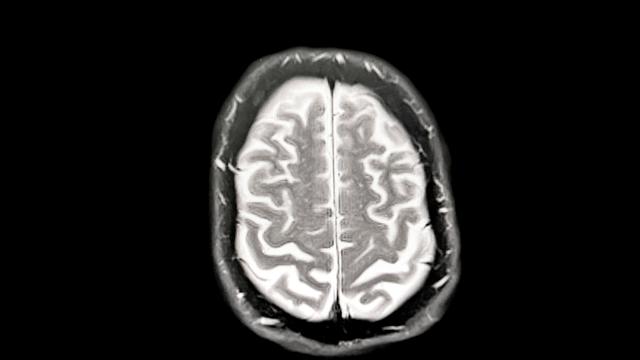

V Nemčiji je od danes naprej na voljo novo zdravilo Leqembi, ki cilja na vzroke Alzheimerjeve bolezni. Zdravilo Lecanemab deluje tako, da pomaga v zgodnjih fazah bolezni, vendar ni primerno za vse bolnike. Strokovnjaki opozarjajo, da zdravilo ne bo pomagalo vsem bolnikom.